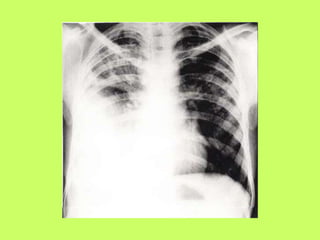

INSTRUMENTAL DIAGNOSTICS

1. Radiological study (including side position) - fluid that excesses 100

ml causes opacity of posterior costodiaphragmatic recess or indistinct

contours of diaphragm.

When volume of effusion increases shadow with oblique or

horizontal level appears.

When effusion is significant, symptoms of mediastinum shift

appear.